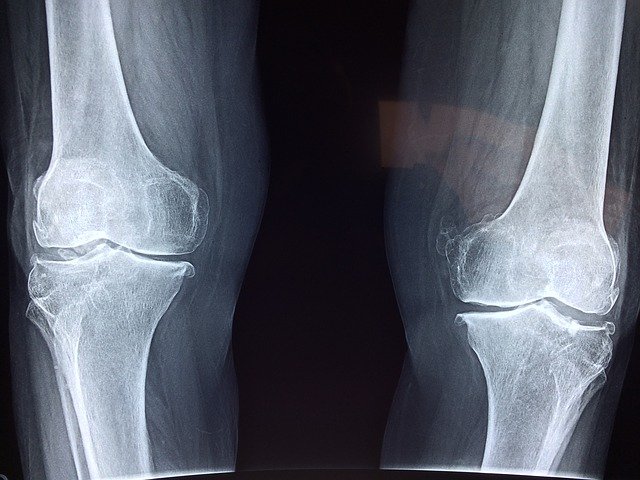

안녕하세요. 오늘은 콘드로이친에 대해서 알아보겠습니다. 콘드로이친은 방송에서 소개가 되면서 많은 사람들에게 인식이 되었습니다. 저도 평소에 콘드로이친이란 단어를 들어보지 못했는데, 방송을 통해서 알게 됐습니다. 콘드로이친 연골 및 뼈에 도움이 된다고 소개가 되면서 무릎이 좋지 않은 많은 분들에게 관심이 됐습니다. 관절에 특히나 도움이 된다는 이 콘드로이친 효능과 콘드로이친 부작용에 대해서 알아보겠습니다.

콘드로이친은 연골과 뼈, 힘줄, 근육, 인대에 도움을 주는 성분으로써, 무릎 관절의 연골 성분과 동일하다고 하여 연골의 그리스어인 콘드로이친으로 불리게 된 것입니다. 연골은 관절이 흔들리지 않도록 고정하는 역할을 하여 부드럽고 편리하게 움직임이 가능하도록 도와줍니다. 연골의 주성분인 콘드로이친 역시 연골이 받은 충격을 흡수하고, 연골의 마찰을 감소시켜 손상을 막아 연골을 보호하는 게 콘드로이친의 주된 역할입니다.

코드로이친의 가장 대표적인 효능이라면 위에서 언급한 것처럼 연골세포의 보호가 아닐까 싶습니다. 콘드로이친에는 연골세포의 분해를 억제시켜주는 효능이 있어서 연골 세포를 보호해주고 유지시켜주는 기능을 수행한다고 합니다. 연골은 노화가 진행될수록 그리고 나이가 점점 들수록 그 크기가 감소하거나 끊어질 수 있다고 하는데 콘드로이친이 그 스펀지와 같은 역할을 하면서 연골 속 안에 있는 수분을 잡아주며 부드럽고 유연하게 유지할 수 있도록 도와준다고 합니다.

콘드로이친은 관절의 통증을 완화하는데 큰 효과가 있다고 합니다. 콘드로이친은 연골에 영양을 공급해줄뿐만 아니라 관절 마찰을 줄이는데도 도움을 주고 연골의 마모가 진행되는 것을 늦춰주는 역할을 한다고 합니다. 그로 인해서 무릎 통증을 줄여주고, 손 관절 통증도 완화해주고 신체의 관절 기능을 향상하는데 큰 도움이 된다고 합니다. 이뿐만 아니라 콘드로이친은 연골에 수분을 끌어들이는 역할을 하여 연골의 탄력성을 증가시켜주어 연골 보호와 유지에 탁월한 효능을 발휘한다고 합니다.